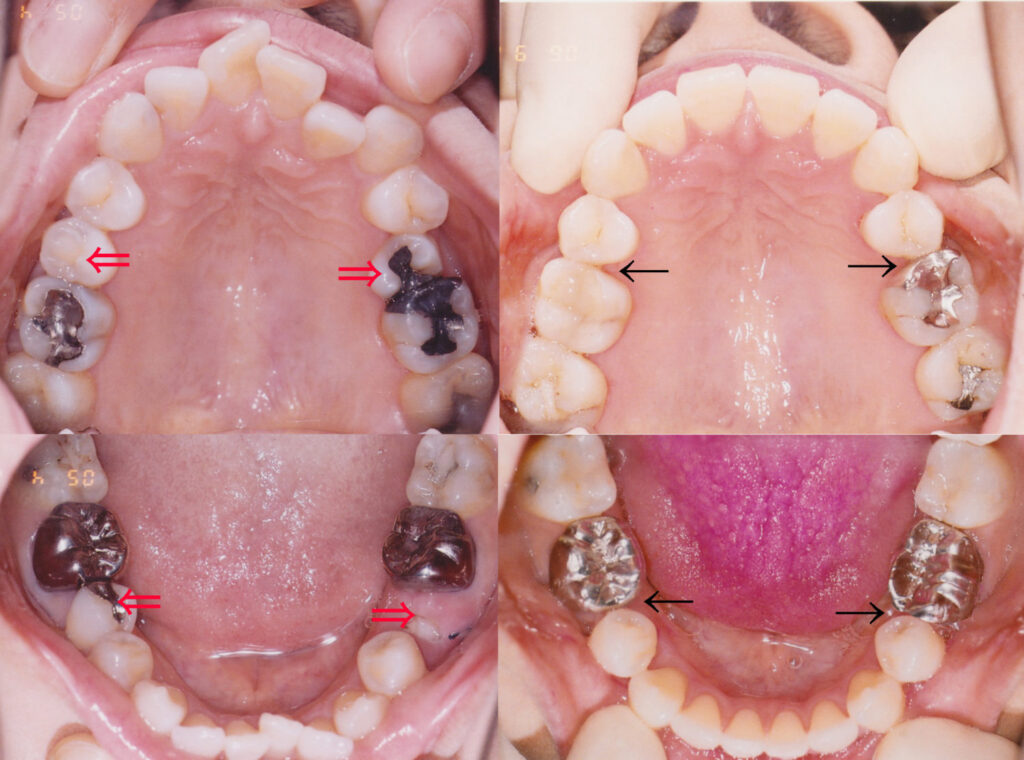

画像説明 : ①主訴 : 上の前歯の並び ②診断名あるいは主な症状 : 左下第二小臼歯の歯冠崩壊を伴…